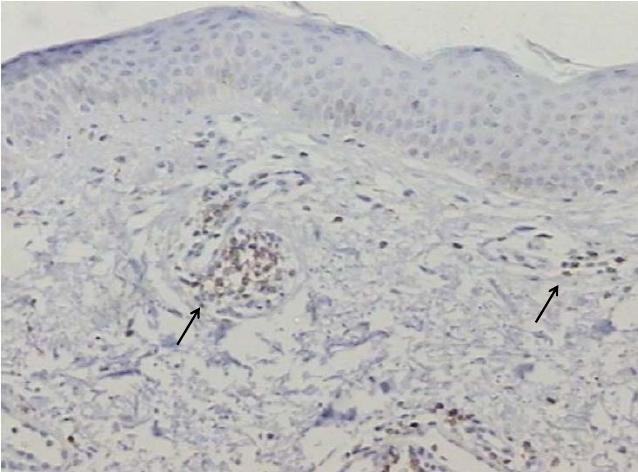

CD4 Ausente 0 0,0 1 11,1 0 0,0 0,4346

Raras 0 0,0 1 11,1 2 50,0

Leve 2 25,0 1 11,1 1 25,0

Moderado 2 25,0 2 22,2 0 0,0

Intenso 4 50,0 4 44,4 1 25,0

Total 8 100,0 9 100,0 4 100,0